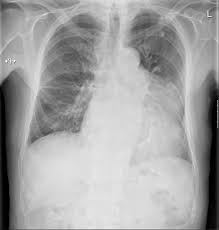

This type of effusion is empyema unless proven otherwise. The most prominent finding of this scan is a loculated pocket of pleural fluid that does not otherwise appear to extend inferiorly between the right lower lobe and the diaphragm. Cxr = chest x ray; Pleural effusion in other conditions classified elsewhere. Cxr loculated right pleural effusion. Read more 3 doctors agree Pleura inflammation, causing sharp pain with breathing; A right thoracentesis was performed, and on seeing the biochemistry results, the left side was also punctured. There is a large left pleural effusion obscuring the lower half of the left hemi thorax. The hilum is visible through the mass. 1 article features images from this case 20 public playlist include this case Malignant pleural effusion, breast carcinoma, maliganancy: Bilateral pleural effusion (bpe) is not an uncommon finding in clinical practice.

It detects pleural effusions with higher sensitivity and specificity than cxr, and provides valuable information about the size and depth of the pleural effusion, the echogenicity of the fluid, the presence of septated or loculated fluid, pleural thickening and nodularity, and the presence of any contralateral pleural effusion. Fluid gathers in the lowest part of the chest, according to the patient's position. A chest tube (12f) was inserted under imaging guidance into the largest locule. Surgical thoracostomy tube placement and radiologically guided catheter drainage are standard therapy for loculated pleural fluid collections. Icu patients cannot sit up and the effusion layers posteriorly. Normally, a small amount of fluid is present in the pleura. Pleural effusion is an abnormal accumulation of fluid in the pleural space. Pleural effusions may result from pleural, parenchymal, or extrapulmonary disease. 1 article features images from this case 3 public playlist includes this case Malignant pleural effusion, breast carcinoma, maliganancy: Loss of right diaphragmatic and cardiac silhouettes. Pa chest radiograph reveals a mediastinal mass, which is in continuity with the left heart border. So pleural effusion is seen on a chest x.

This type of effusion is empyema unless proven otherwise. Pa chest radiograph reveals a mediastinal mass, which is in continuity with the left heart border. An anechoic effusion can be a transudate or exudate (fig. Pleural effusion in other conditions classified elsewhere. Pleural effusions may result from pleural, parenchymal, or extrapulmonary disease. So pleural effusion is seen on a chest x. Pfa = pleural fluid analysis. In chf effusions are bilateral and more on right. L effusion, loculations, vats, empyema: Loculated right pleural effusion with foci of atelectasis and consolidative changes concerning for pneumonia. The pleura are thin membranes that line the lungs and the inside of the chest cavity and act to lubricate and facilitate breathing. Surgical thoracostomy tube placement and radiologically guided catheter drainage are standard therapy for loculated pleural fluid collections. 1 article features images from this case 3 public playlist includes this case